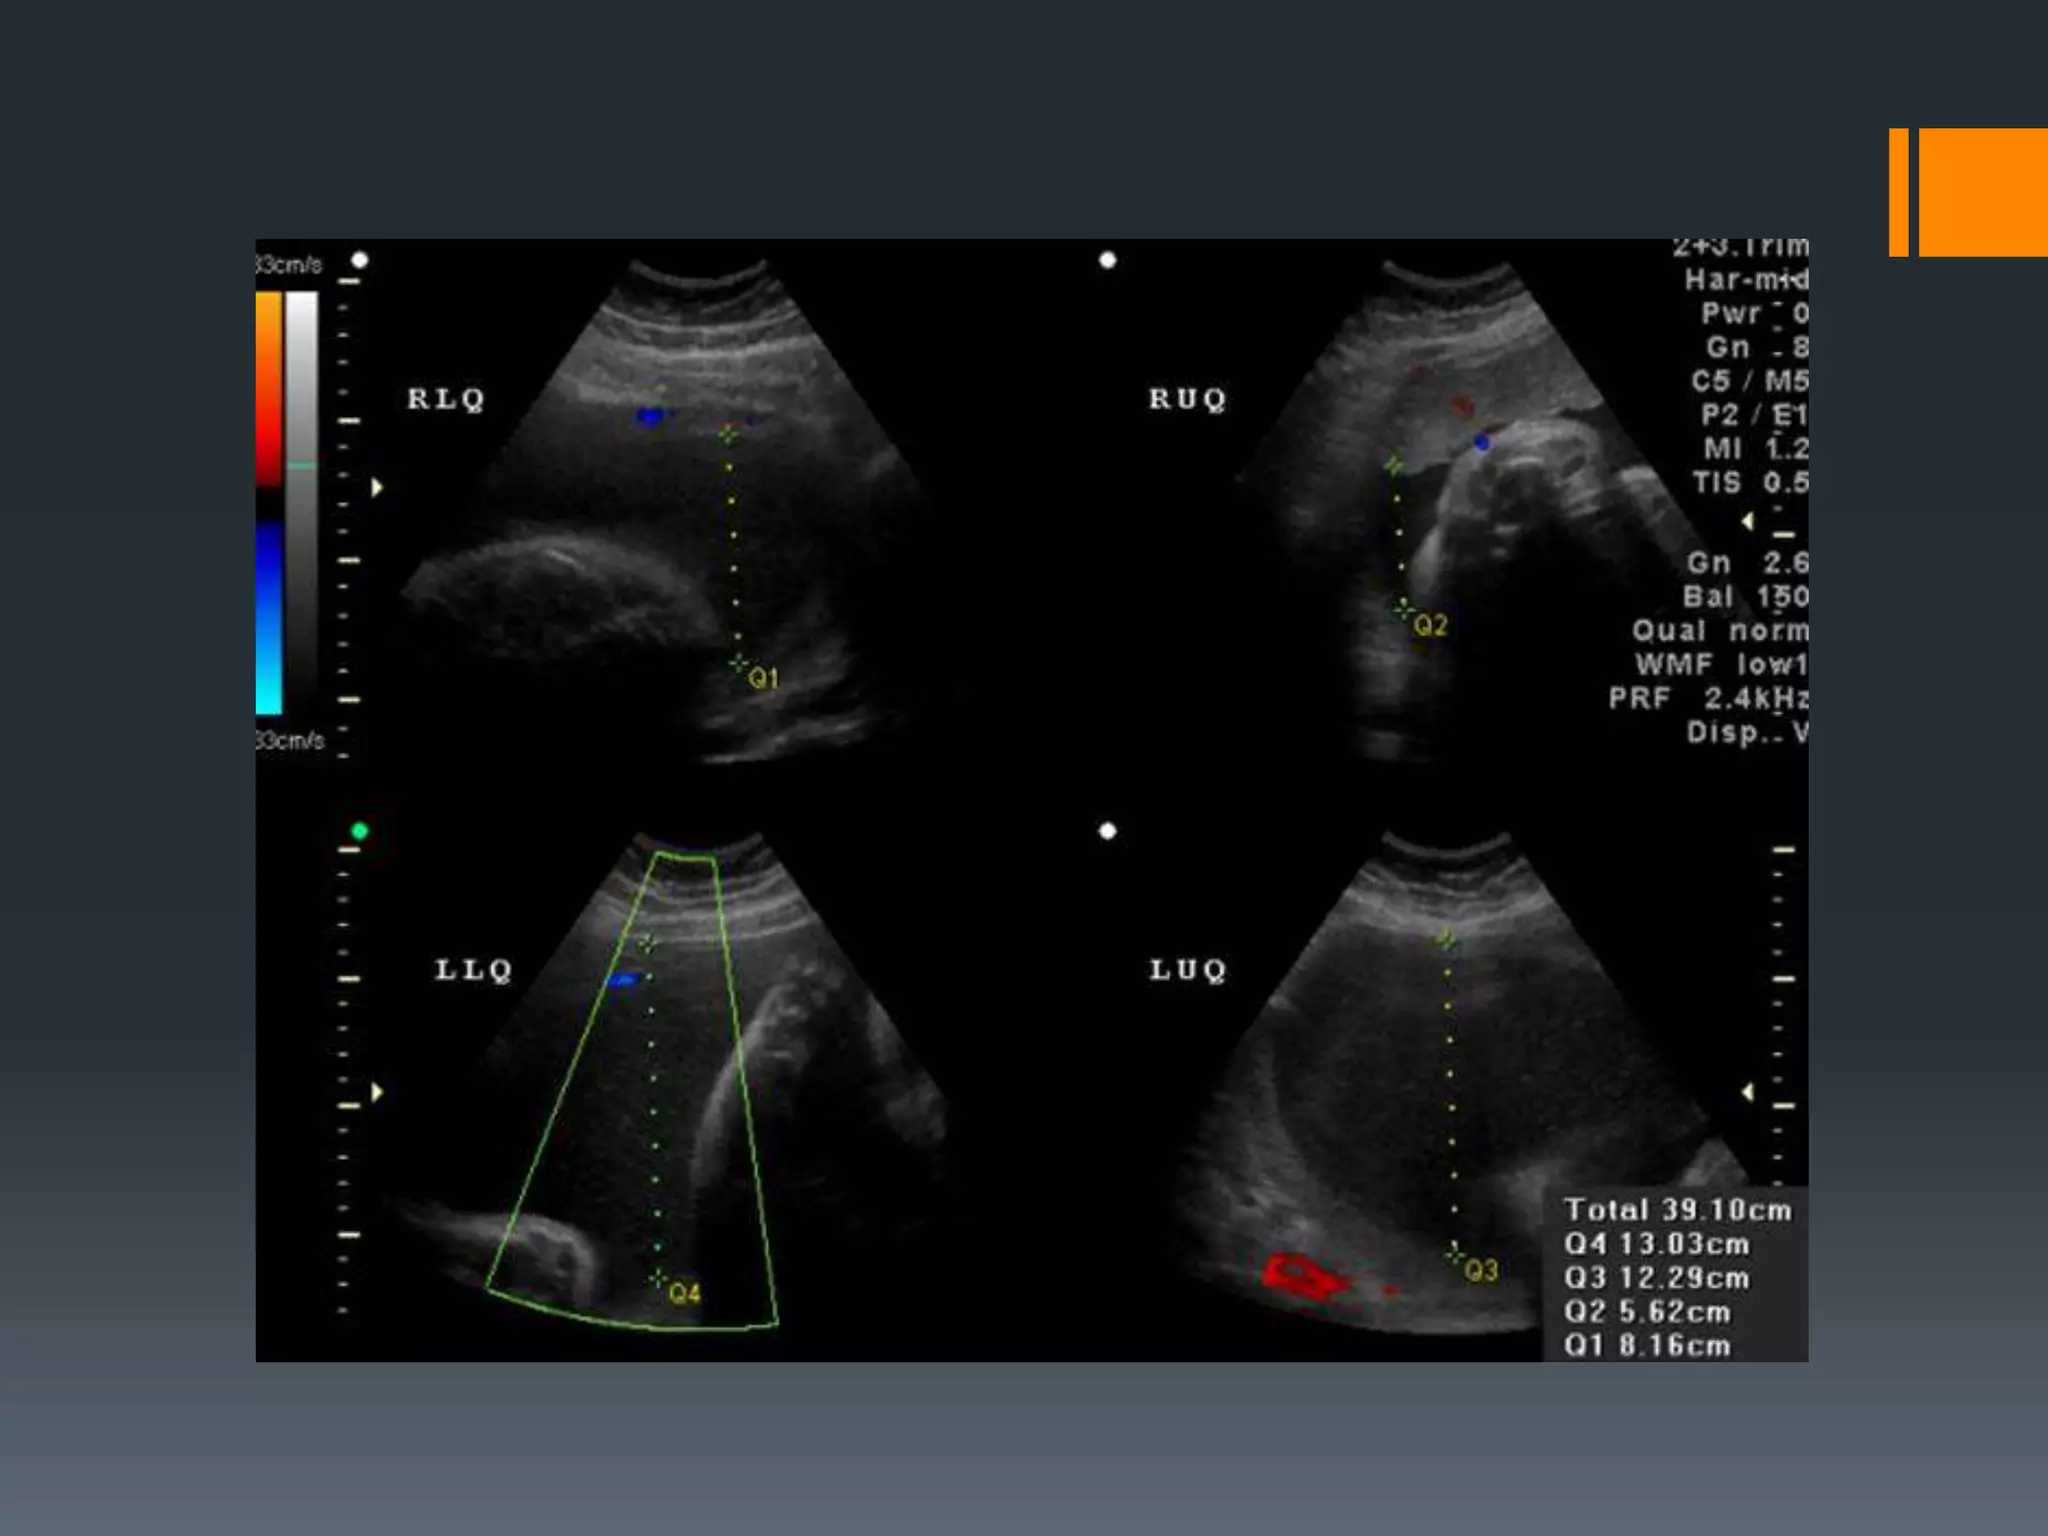

AFI

• Volume of AF is evaluated by visually dividing the

mother's abdomen into 4 quadrants

• The largest vertical pocket of fluid in each

quadrant is measured in cm

• Cord containing pocket < 30%

• Total volume is calculated by adding these values

• < 5 oligohydramnios

o AFI < 5.0 cm had a sensitivity of 18% for the detection of

oligohydramnios

• 6-8 borderline AFI

• 8-24 normal

• > 24 polyhydramnios

AFI • Volume ofAF is evaluated by visually dividing the mother's abdomen into 4 quadrants • The largest vertical pocket of fluid in each quadrant is measured in cm • Cord containing pocket < 30% • Total volume is calculated by adding these values • < 5 oligohydramnios o AFI < 5.0 cm had a sensitivity of 18% for the detection of oligohydramnios • 6-8 borderline AFI • 8-24 normal • > 24 polyhydramnios